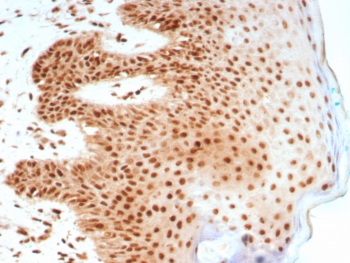

Nucleolin Antibody Rabbit Monoclonal NCL/8695R immunohistochemistry analysis of human skin tissue. Formalin-fixed paraffin-embedded human skin stained with Nucleolin Antibody Rabbit Monoclonal NCL/8695R. HRP-DAB brown chromogenic staining highlights nuclei of epidermal epithelial cells, consistent with the expected nuclear and nucleolar localization of Nucleolin / NCL. HIER: boil tissue sections in pH 9 10mM Tris with 1mM EDTA for 20 minutes and allow to cool before testing.